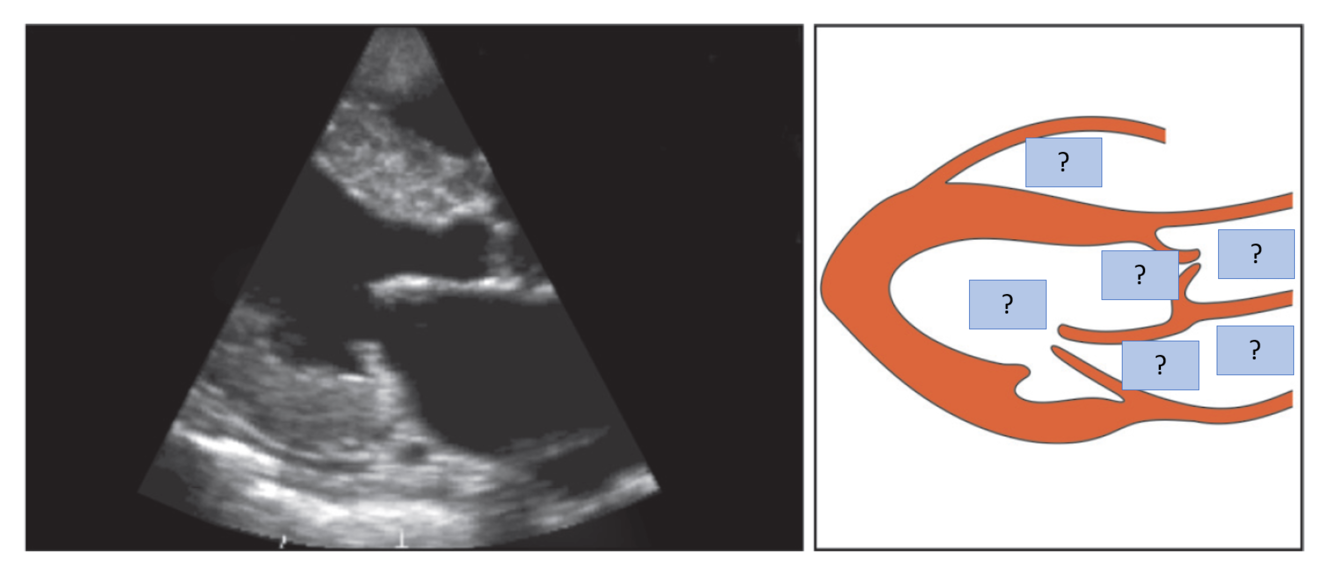

Q

A

Transducer position to obtain parasternal long-axis view?

Marker dot position?

Transducer position: left sternal edge; 2nd–4th space

Marker dot direction: points towards right shoulder

Which view do most echo studies begin with?

Parasternal Long Axis (PLAX)